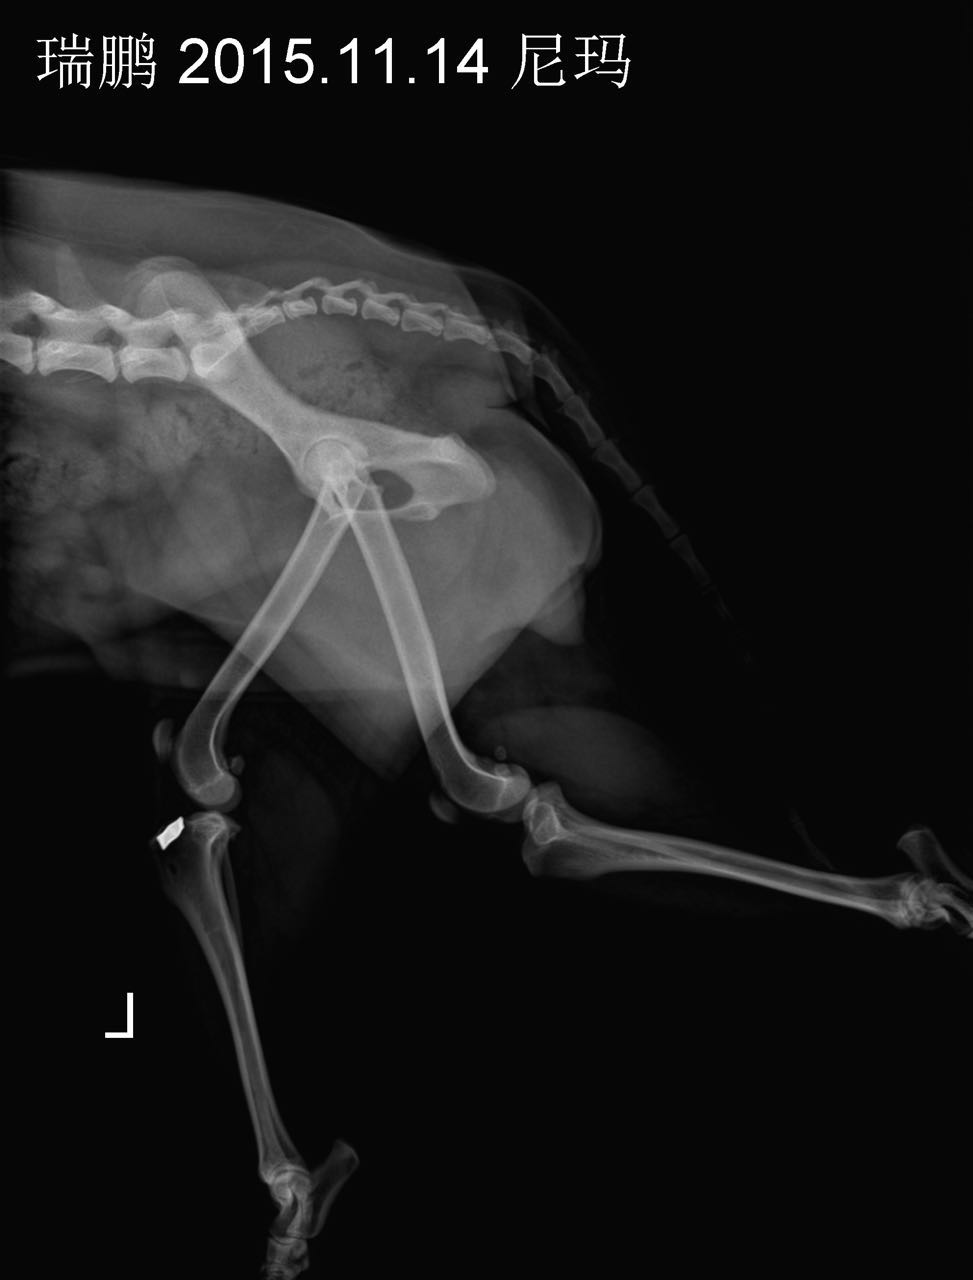

摘 要:动物发生脊椎骨折一般是由大的外力所致:如咬伤、车祸伤或高楼坠伤